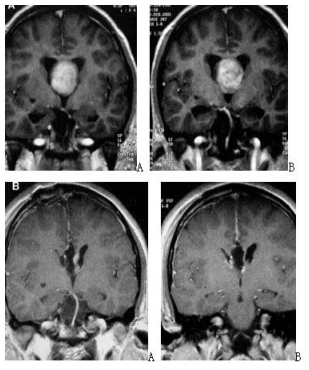

Figure 10. preoperative and postoperative imaging of endoscopic resection of interventricular foramen gumbo cyst via lateral ventricular frontal horn-interventricular foramen approach. A and B: preoperative images; c and d: postoperative images showing complete tumor resection.

Figure 12. A and B preoperative images; C and D postoperative images.